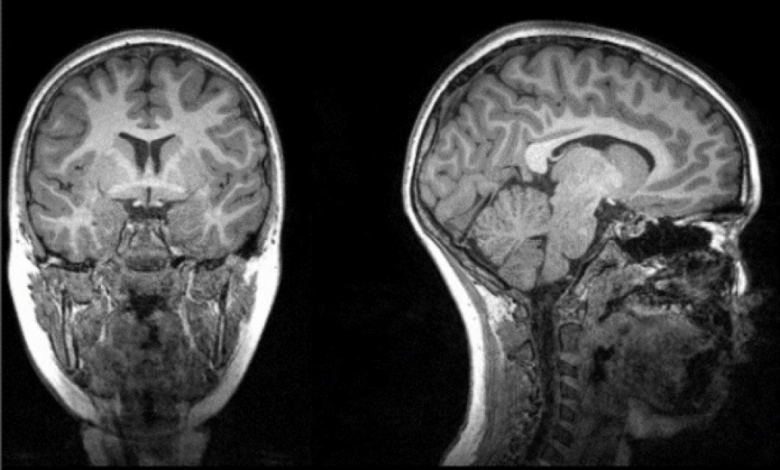

Los investigadores analizaron tomografías computarizadas en 120 pacientes neurológicos, incluidos 58 con COVID-19 agudo y 62 sin COVID-19, emparejados por edad, sexo y enfermedad. El trabajo se realizó conjuntamente con Enrico Premi y sus colegas de la Universidad de Brescia (Italia), que proporcionaron los datos para el estudio. Utilizaron un análisis de morfometría basado en la fuente, que aumenta la potencia estadística de los estudios con un tamaño de muestra moderado.

«La ciencia ha demostrado que la estructura del cerebro afecta a su función, y las imágenes cerebrales anormales han surgido como una característica importante de la COVID-19. Estudios anteriores han examinado cómo el cerebro se ve afectado por COVID-19 utilizando un enfoque univariante, pero el nuestro es el primero en utilizar un enfoque multivariante, basado en datos, para vincular estos cambios a las características específicas de COVID-19 (por ejemplo, la fiebre y la falta de oxígeno) y el resultado (nivel de discapacidad)», explica el doctor Kuaikuai Duan, uno de los autores de la investigación.

El análisis mostró que los pacientes con mayores niveles de discapacidad tenían un menor volumen de materia gris en los giros frontales superior, medial y medio en el momento del alta y seis meses después, incluso cuando se controlaban las enfermedades cerebrovasculares.

El volumen de materia gris en esta región también se redujo significativamente en los pacientes que recibían oxigenoterapia en comparación con los que no la recibían. Los pacientes con fiebre presentaron una reducción significativa del volumen de materia gris en los giros temporales inferior y medio y en la circunvolución fusiforme en comparación con los pacientes sin fiebre. Los resultados sugieren que la COVID-19 puede afectar a la red frontal-temporal a través de la fiebre o la falta de oxígeno.